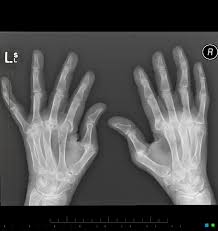

Rheumatoid arthritis manifests as a symmetrical arthritis, most commonly affecting the hands. The 2010 rheumatoid arthritis classification criteria help doctors diagnose rheumatoid arthritis. It typically results in warm, swollen, and painful joints. </b>small joints of the feet, wrists, and hands are frequently involved by a reduction of osteoporosis; Pain and stiffness often worsen following rest.

If the pattern of disease is not symmetrical, then a different diagnosis should be considered. Imaging tests you may get. The 2010 rheumatoid arthritis classification criteria help doctors diagnose rheumatoid arthritis. The ulnar styloid is destroyed with the rest of the distal ulna (white arrow), there is destruction of the carpal bones (yellow arrow) and there is dislocation of the 1st metacarpal on the destroyed trapezium. It can affect anyone of any age. Rheumatoid arthritis (ra) is a chronic autoimmune multisystemic inflammatory disease that affects many organs but predominantly attacks the synovial tissues and joints. Rheumatoid arthritis affects around 400,000 adults aged 16 and over in the uk. Rheumatoid arthritis can be difficult to diagnose because many conditions cause joint stiffness and inflammation and there's no definitive test for the condition. Ra causes pain, swelling, stiffness, and loss of function in joints. Rheumatoid arthritis is an inflammatory arthritis affecting both small and large joints in a symmetric distribution. Rheumatoid arthritis is an immune system condition, or autoimmune disorder, that causes inflammation of the lining of the joints. Rheumatoid arthritis is a chronic inflammatory disorder that can affect more than just your joints. Rheumatoid arthritis manifests as a symmetrical arthritis, most commonly affecting the hands.

Rheumatoid arthritis (ra) is the most common type of autoimmune arthritis. Rheumatoid arthritis (ra) is a chronic autoimmune multisystemic inflammatory disease that affects many organs but predominantly attacks the synovial tissues and joints. If the pattern of disease is not symmetrical, then a different diagnosis should be considered. It typically results in warm, swollen, and painful joints. Reddit gives you the best of the internet in one place. </b>rheumatoid arthritis (ra) is a polyarticular disease with bilateral and symmetric distribution. Rheumatoid arthritis (ra) imaging tests are used to look for signs of ra and to monitor the disease's progression. Rheumatoid arthritis is considered an indication for resurfacing of the patella during total knee arthroplasty.

Rheumatoid arthritis is an inflammatory arthritis affecting both small and large joints in a symmetric distribution.